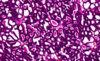

באיזה שלב הביצית בתמונה?

mature graafian follicle

corpus hemorrhagicum